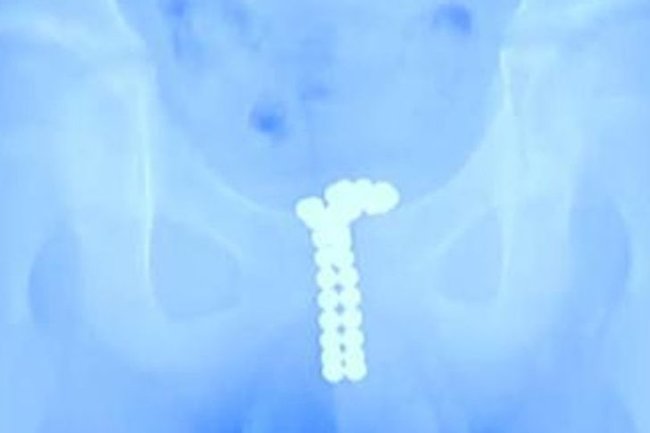

Belə ki, qarnındakı şiddətli ağrılara görə həkimə aparılan uşaq həkimlər tərəfindən müayinə edilib. Rentgen yoxlanışı zamanı uşağın cinsiyyət orqanında 39 metal muncuqların toplandığını ortaya çıxıb.

Dərhal əməliyyata qaldırılan uşağın cinsiyyət orqanına yığılan metal muncuqlar çıxarılıb. Hazırda uşağının səhhətinin normal olduğu bildirilir.